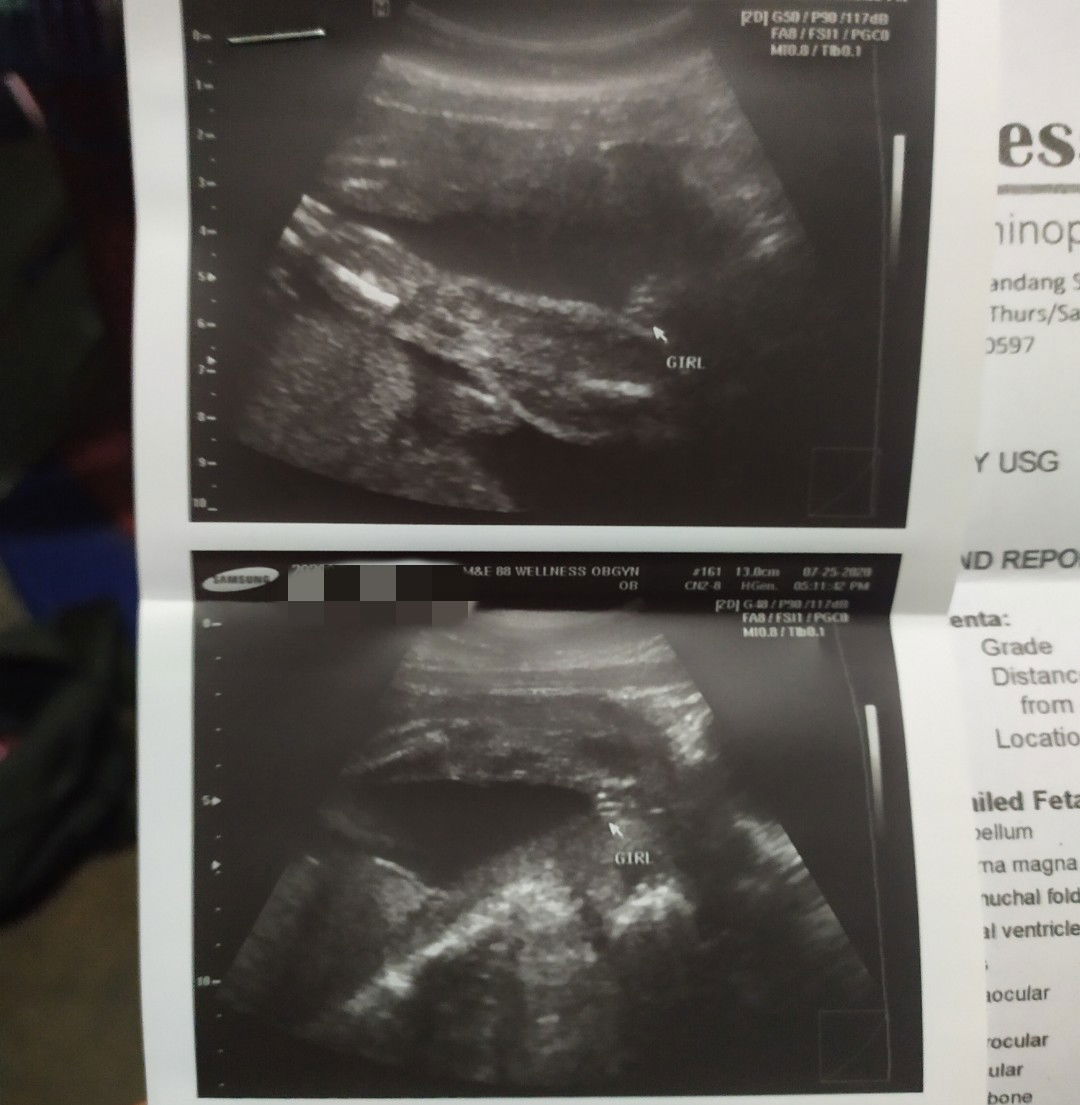

BABY GIRL NAME

Hi mga momsh! Suggest po kayo ng baby girl name start with Letter C. Thaanks💕